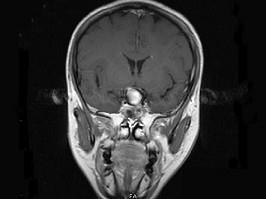

女,43岁,反复头痛10个月,CT检查如图,最可能诊断为 ( )A、脑膜瘤B、胶质瘤C、垂体瘤D、颈内动脉瘤E、颅咽管瘤

问题 女,43岁,反复头痛10个月,CT检查如图,最可能诊断为 ( )

选项 A、脑膜瘤 B、胶质瘤 C、垂体瘤 D、颈内动脉瘤 E、颅咽管瘤

答案 D